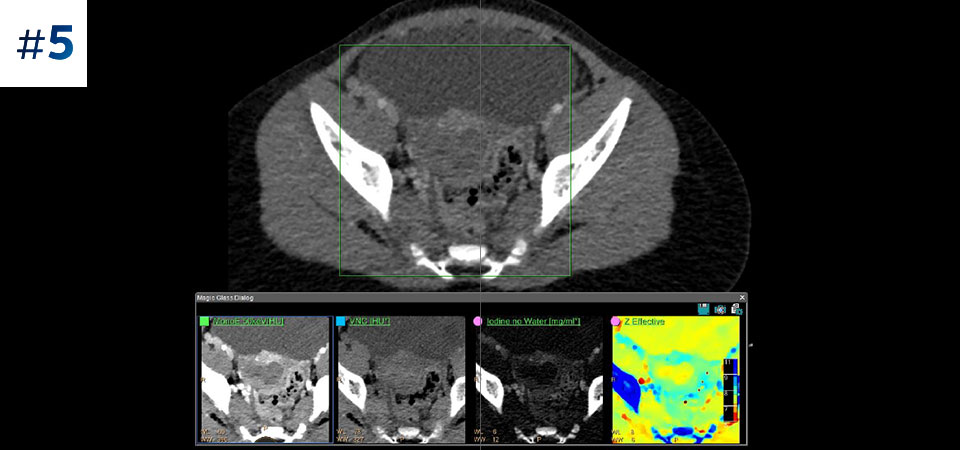

Umflătură la nivelul gâtului